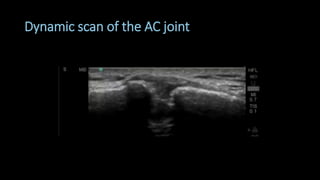

Superior scanning protocol

• Dynamic scan

• Have the patient move the hand

to the contralateral shoulder

• Look for:

• Separation

• Irregularity in bony margins

• Osteoarthritis

• “Geyser phenomenon”

• Bursal fluid moving upwards

Dynamic scan of the AC joint